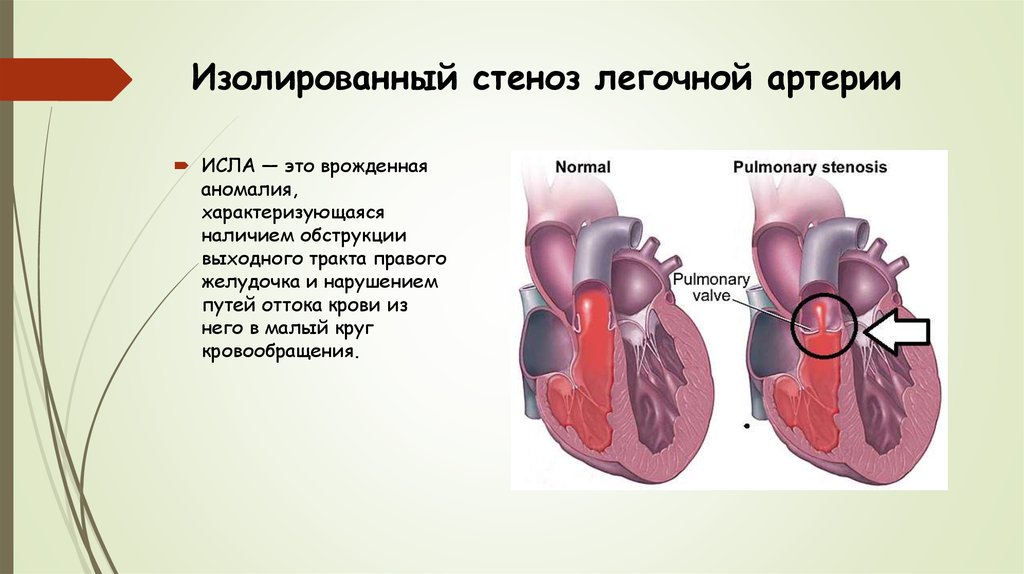

Пороки сердечно-сосудистой системы: виды и признаки